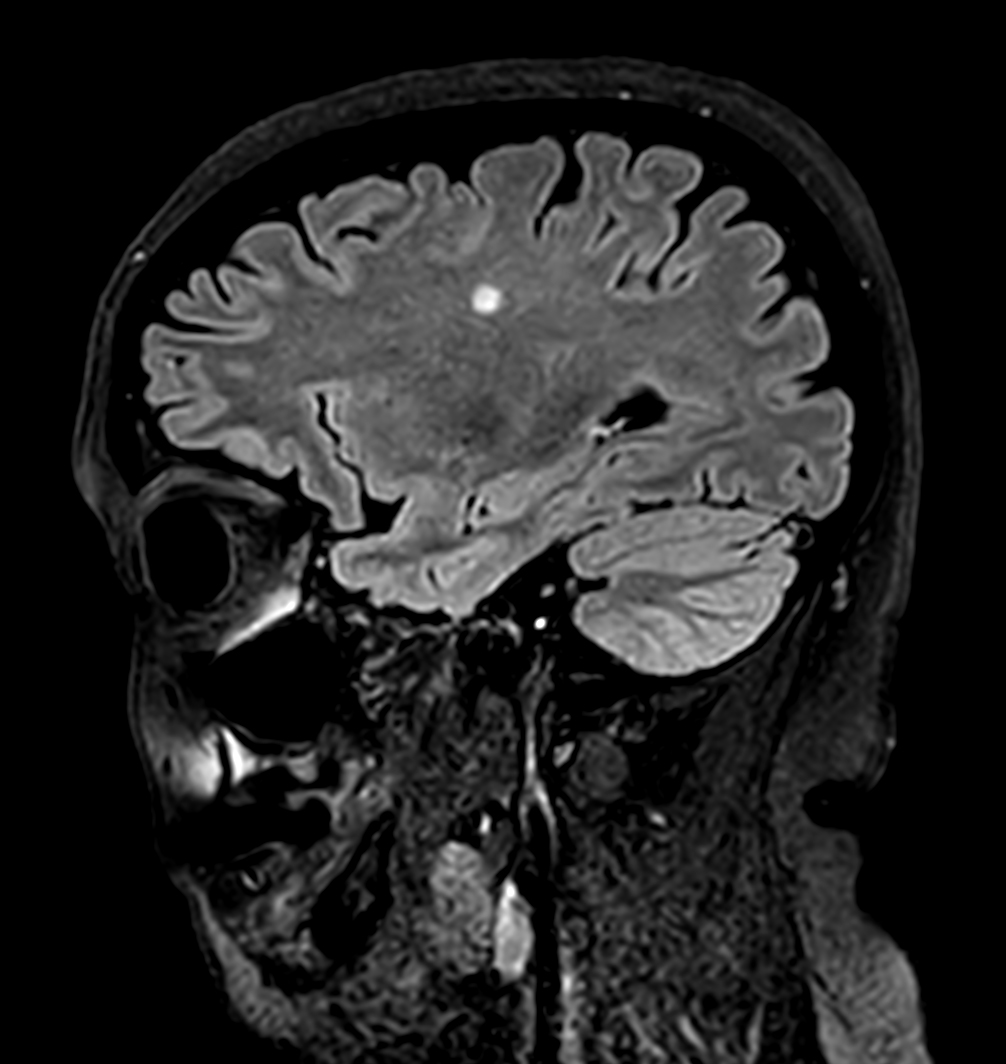

Sagittal 3D BrainVIEW FLAIR